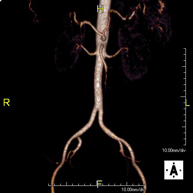

Prova diagnòstica no invasiva que consisteix en l'obtenció d'imatges d'alta definició anatòmica de tot el cos mitjançant l'ús d'un camp electromagnètic i ones de ràdio (amb un emissor i un receptor). No utilitza radiació ionitzant. És una prova molt important en la recerca de metàstasi en pacients amb neoplàsia coneguda. No requereix preparació prèvia. No és necessari l'ús de contrast paramagnètic (Gadolini). - Angio RM d'Aorta-ilíaca

Prova diagnòstica no invasiva que consisteix en l'estudi de l'artèria aorta abdominal i de les artèries ilíaques, amb l'obtenció d'imatges d'alta definició anatòmica mitjançant l'ús d'un camp electromagnètic i ones de ràdio (amb un emissor i un receptor). És indispensable l'ús de contrast paramagnètic (Gadolini). No utilitza radiació ionitzant. La qualitat de les imatges permet realitzar reconstruccions en 2D i 3D. Aquesta prova està especialment indicada com a estudi prequirúrgic (mapa vascular) abans d'intervencions percutànies o quirúrgiques d'aorta abdominal i artèries ilíaques, per a l'estudi complementari en pacients amb isquèmia de membres inferiors, etc. - Angio RM Arterial d'extremitats inferiors

Prova diagnòstica no invasiva que consisteix en l'obtenció d'imatges d'alta definició anatòmica de l'aorta toràcica (principal artèria del tòrax) mitjançant l'ús d'un camp electromagnètic i ones de ràdio (amb un emissor i un receptor). No utilitza radiació ionitzant. En la majoria dels casos és necessari l'ús de contrast paramagnètic (Gadolini). Permet un estudi angiogràfic no invasiu gràcies a la injecció de Gadolini amb posterior reconstrucció en 2D i 3D, mitjançant estacions de treball especialitzades. També inclou l'estudi de la vàlvula aòrtica, informació imprescindible en el cas que el pacient necessiti cirurgia. Aquesta prova està especialment indicada en pacients que requereixen tractament quirúrgic (com a mapa vascular prequirúrgic), en el seguiment de pacients amb aneurismes d'aorta, etc. - Angio-RM d'Aorta Abdominal

Prova diagnòstica no invasiva que consisteix en l'estudi de l'artèria aorta abdominal per obtenir imatges d'alta definició anatòmica mitjançant l'ús d'un camp electromagnètic i ones de ràdio (amb un emissor i un receptor). És indispensable l'ús de contrast intravenós paramagnètic (Gadolini). No obstant, no utilitza radiació ionitzant. La qualitat de les imatges permet realitzar reconstruccions en 2D i 3D. Està indicat en aquells pacients amb malaltia vascular (Aterosclerosi), per a l'estudi d'aneurismes, en estudis prequirúrgics de lesions adjacents a l'aorta abdominal com "mapa" vascular, etc. - Angio-RM Aorta ilíaca

Prova diagnòstica no invasiva que consisteix en l'estudi de l'artèria aorta abdominal per obtenir imatges d'alta definició anatòmica mitjançant l'ús d'un camp electromagnètic i ones de ràdio (amb un emissor i un receptor). És indispensable l'ús de contrast intravenós paramagnètic (Gadolini). No obstant, no utilitza radiació ionitzant. La qualitat de les imatges permet realitzar reconstruccions en 2D i 3D. Aquesta prova està especialment indicada com estudi prequirúrgic (mapa vascular) abans d'intervencions percutànies o quirúrgiques d'aorta abdominal, per a l'estudi complementari en pacients amb isquèmia de membres inferiors, etc. - Angio-RM d'Artèries renals